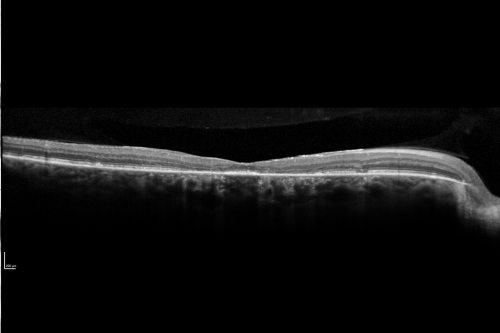

Fundus Flavimaculatus - Stargardt Disease - 20/50 OD 20/200 OS 61 Year old - SD OCT OD

61-year-old decreasing vision for about the last five years. OD 20/50, OS 20/200.

Pisciform Lesions and Macular Atrophy